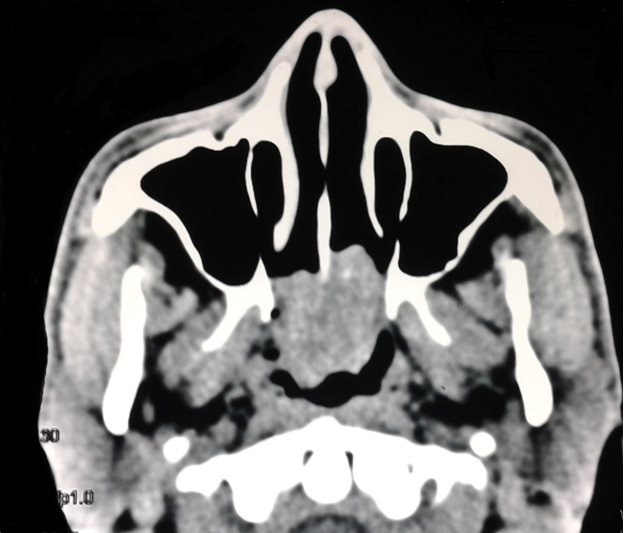

A 25year old man presented with history of progressive bilateral nasal obstruction and snoring for the past two years. There was no history of nasal discharge, post nasal drip, nasal bleeding and his wife reported difficulty in sleeping in the same room with the patient due to snoring. Anterior rhinoscopy was normal. On diagnostic nasal endoscopy a lobulated mass arising from the superior aspect of posterior septum on left side, obstructing whole of the choana was seen (Figure 1). Computed tomography revealed a soft tissue mass occupying whole of the nasopharynx abutting the nasal septum (Figure 2). Paranasal sinuses were normal. Patient was taken up for endoscopic excision and biopsy. Local anesthesia was infiltrated in the pedicle and the stalk of the polyp was resected with the small amount of normal surrounding mucosa. The base of the stalk was cauterized with bipolar cautery. No nasal packing was required and patient was discharged on the same day. Macroscopically the mass was of around 5X2X2cm with lobulated surface and multiple firm nodules were palpable over the surface (Figure 3). On cut section white strands were found, along with few cystic areas (Figure 4). Histopathology revealed a polypoidal tissue mass with marked inflammatory infiltrate containing mostly lymphocytes with lack of Stromal edema and goblet cell hyperplasia; these were suggestive of fibroinflammatory polyp. Postoperative period was uneventful. There was no recurrence in the six months follow up.

Figure 1 Endoscopic photograph on left side showing the polyp filling the posterior choana and its attachment on the superior aspect on posterior septum.

Figure 2 CT scan showing the polyp present in nasopharynx abutting the nasal septum. Sinuses are clear.